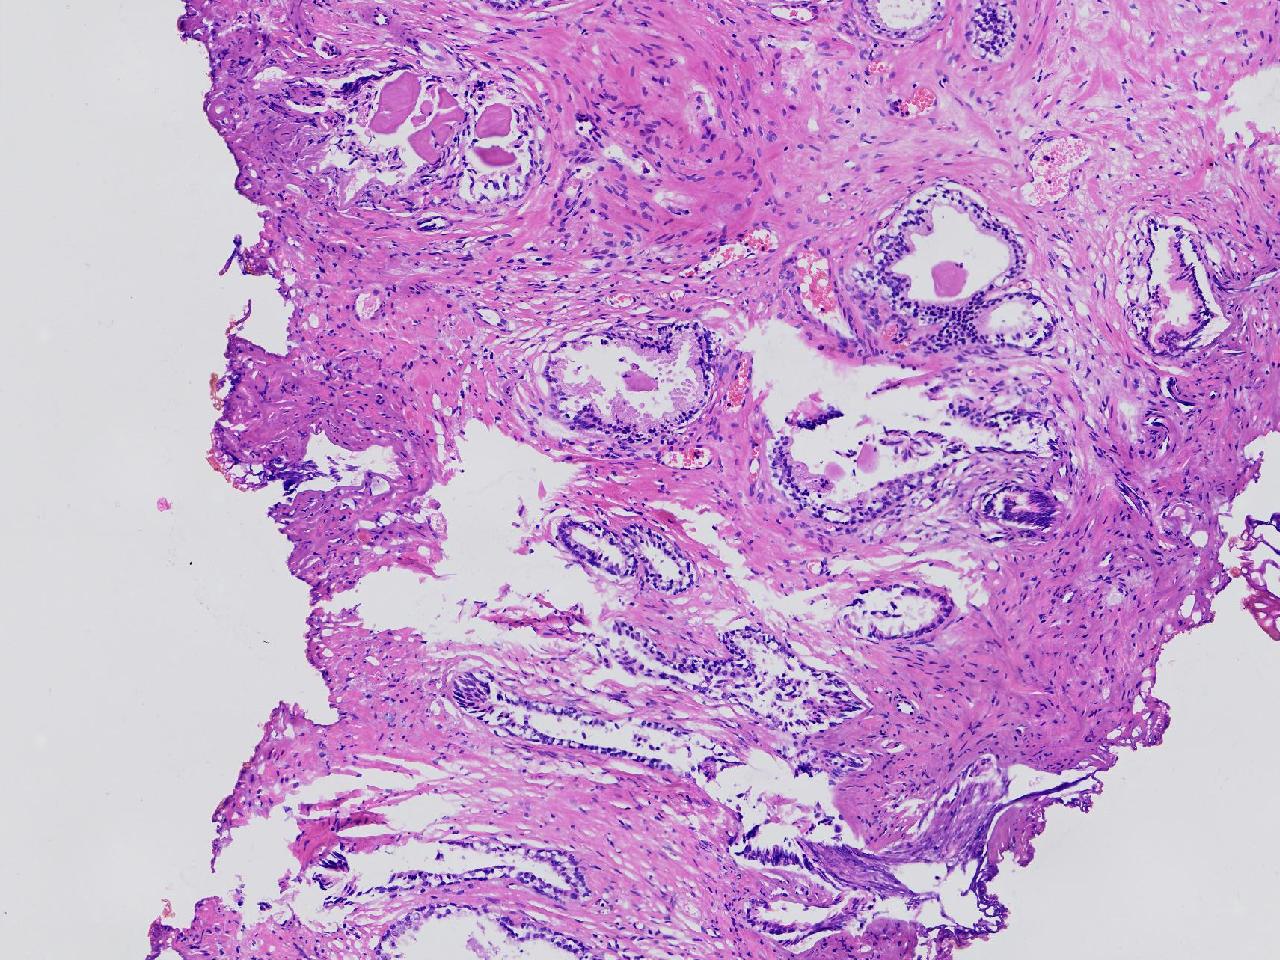

良性前列腺增生?

男,68岁,排尿困难半年余。行前列腺前切术。

前列腺电切标本

灰粉色条索状软组织多块,4X3X3厘米。

考虑为良性前列腺增生症

良性增生

BPH.